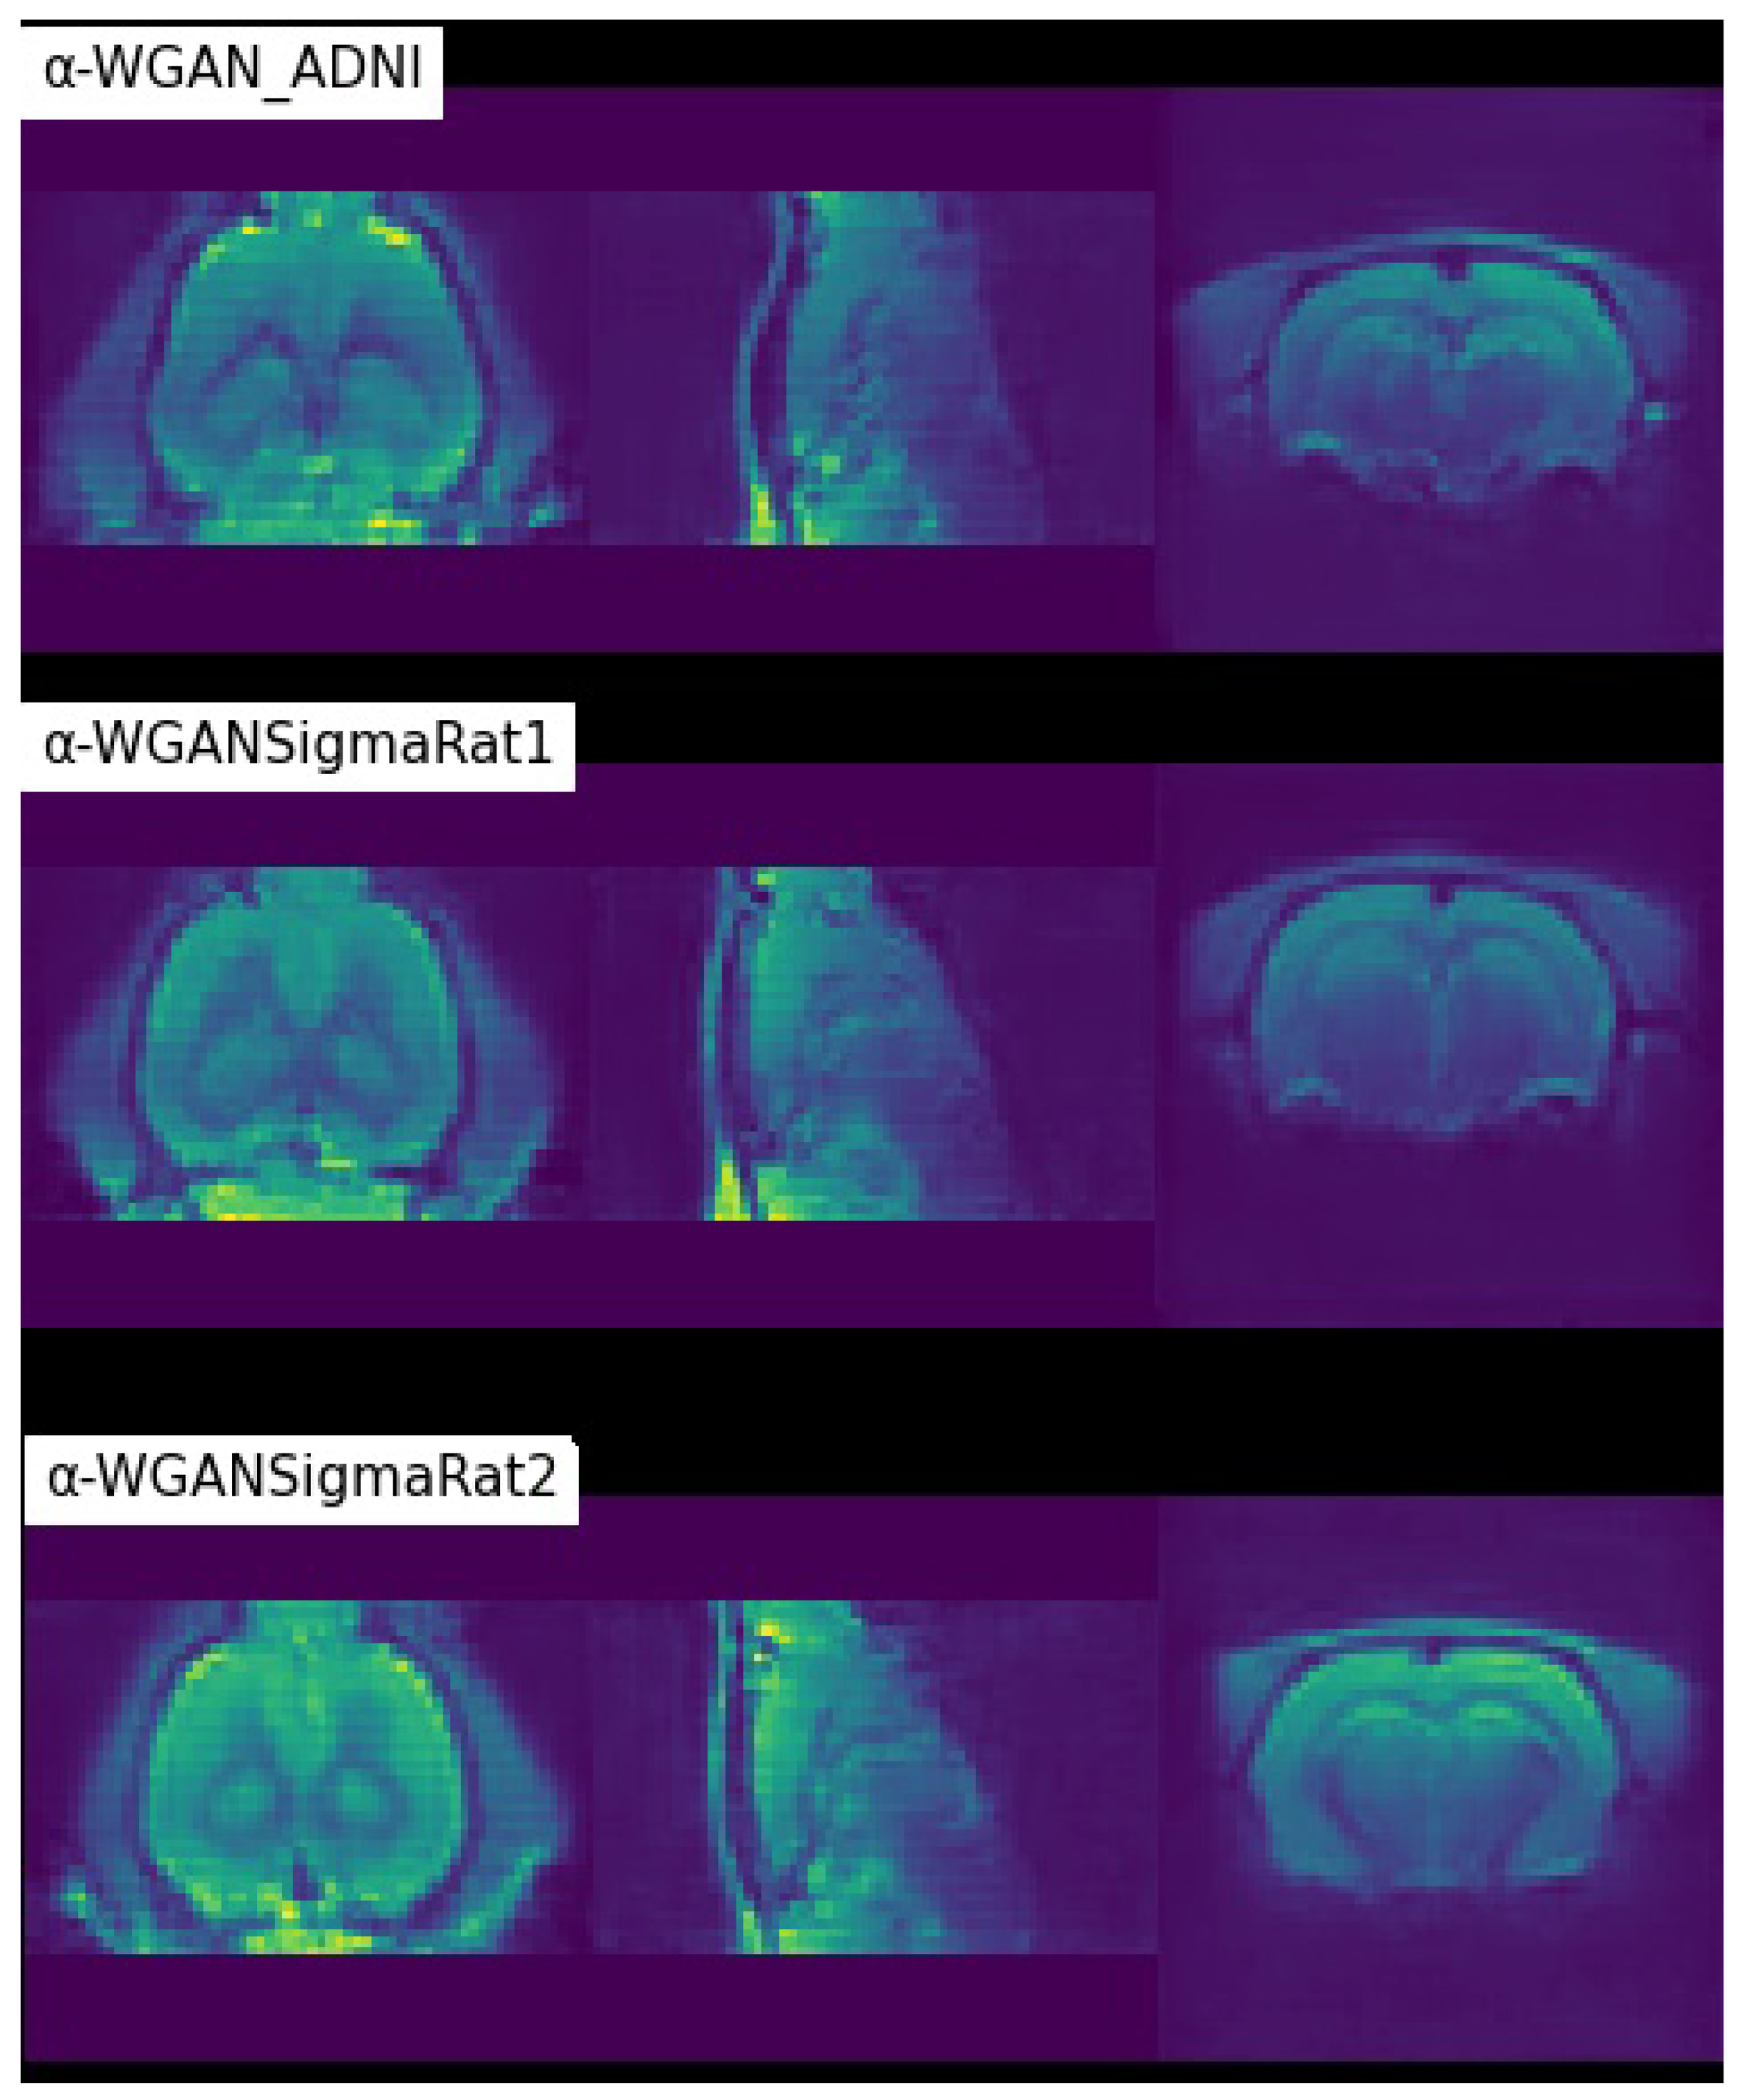

| -WGAN_ADNI [26] | 0.6860 | 0.7241 | 0.0316 | 779.4653 |

| ±0.0066 | ±0.0071 | ±0.0004 | ±27.2016 | |

| -WGANSigmaRat1 | 0.8118 | 0.7887 | 0.0305 | 753.1584 |

| ±0.0051 | ±0.0041 | ±0.0004 | ±24.8816 | |

| -WGANSigmaRat2 | 0.8236 | 0.7527 | 0.0325 | 819.3409 |

| ±0.0056 | ±0.0037 | ±0.0003 | ±20.4437 |